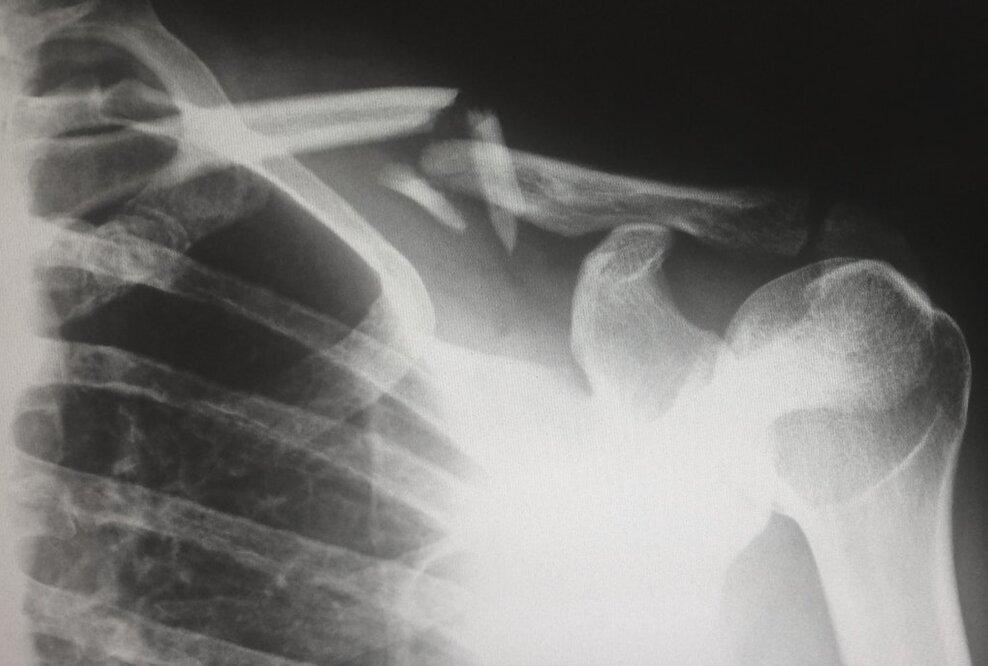

Nervus-Axillaris-Parese nach Schultergelenksoperation, LG Stuttgart, Az.: 15 O 294/16

Die Klägerin befand sich 2015 in der Klinik der Beklagten aufgrund eines Impingement-Syndroms der Schulter rechts. Anlässlich der Schultergelenksoperation kam es zur Schädigung des Nervus Axillaris. Seither leidet die Klägerin unter körperlichen Bewegungsbeeinträchtigungen und Schmerzen und kann auch ihrem Beruf als Fachverkäuferin nicht mehr nachgehen.